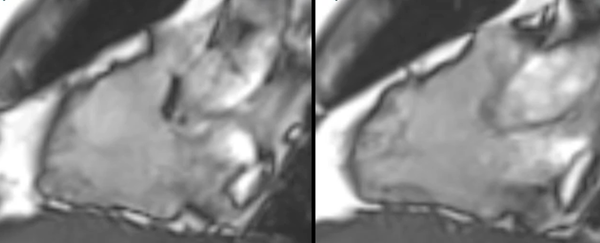

Non-Ischemic Cardiomyopathy

A lecture describing the role of CMR in the various non-ischemic cardiomyopathies